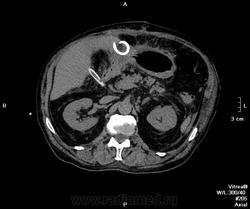

Пациент оперирован по поводу аденоКа толстого кишечника, гемиколэктомия. Онкопоиск, поиск вторичного поражения.

В воротах печени беда, но не об этом сейчас. Прицельно смотрим контраст.

Артериальная.

Венозная.

отсроченные

Во втором случае наблюдается гиподенсный участок в печени.

дифференцируем между метастазом и холангиокарциномой

Случай 2. Опять не попали в фазы, рано. Исследование малоинформативно по сути(. Какова скорость введения автошприцем? Катетер кубитальный или в запястье?